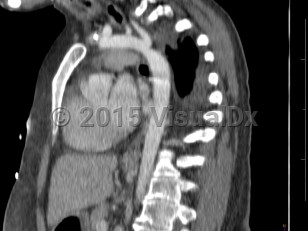

Coarctation of the aorta

Narrowing of the descending aorta distal to the take-off of the great vessels. Posterior costal arteries and internal mammary and scapular arteries provide collateral flow to the descending aorta. Usually congenital, although can be acquired as a consequence of inflammatory diseases affecting the aorta (eg, Takayasu arteritis). Clinical manifestations vary by age and associated cardiac defects, which may include bicuspid aortic valve, atrial septal defect (ASD), ventricular septal defect (VSD), patent ductus arteriosus, and D-transposition of the great vessels.

Aortic coarctation accounts for 5%-8% of all congenital heart defects and may occur as an isolated defect or in combination with ventricular septal defect and bicuspid aortic valve. Infants typically present with signs of heart failure as the ductus arteriosus closes due to significant increase in afterload with left ventricular strain and pulmonary congestion.

Previously undiagnosed children and adults typically present with hypertension. Systolic pressures are usually higher in the upper extremities than in the lower extremities. Femoral pulses are usually diminished or delayed. Lower extremity claudication occurs with exertion. Lower extremity systolic pressures may be unobtainable.